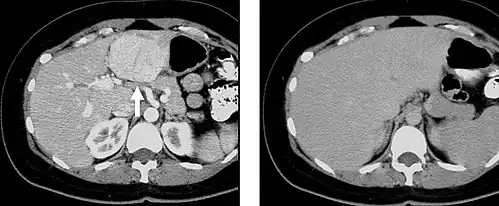

Selected images from a biphasic CT of Focal Nodular Hyperplasia in the left hepatic lobe (arrow). These masses have characteristic early arterial enhancement (6a) with contrast wash out on the portal venous phase images (6b) from the mass making these lesions difficult to identify on portal venous phase images alone.

When evaluating hepatic masses by abdominal computed tomography (CT), it can be advantageous to have both late arterial and portal venous phase images since some tumors enhance briskly during the arterial phase (hepatocellular carcinoma, hepatic adenoma, follicular nodular hyperplasia (FNH), and hypervascular metastasis), but maybe occult or difficult to characterize on portal venous phase imaging alone. However, it should be stressed that the addition of late arterial phase images is only indicated if one of these tumors is suspected, or if there is a need for further characterization of a hepatic mass, since the large majority of patients will not benefit from the addition of this phase. In addition, if there is a need to definitively characterize a hepatic mass, MRI is generally more sensitive and specific, with no associated radiation dose.